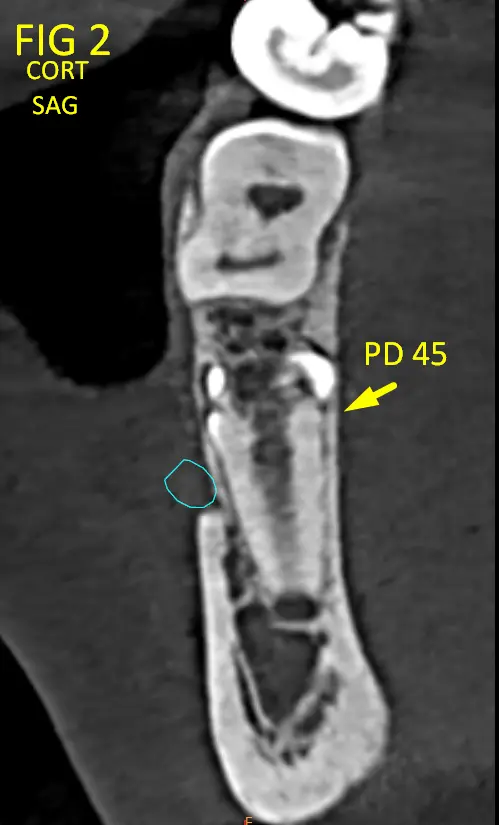

• Pieza 35(Fig. 3) (Fig. 3B): retenida, con orientación en retroversión hacia la base mandibular.

Ambas piezas presentan adaptaciones morfológicas compatibles con modificaciones ocurridas durante la odontogénesis, probablemente condicionadas por el espacio óseo disponible y las presiones locales.

Estas adaptaciones no representan deformaciones patológicas, sino ajustes estructurales del germen dentario frente a un entorno mecánico restrictivo.